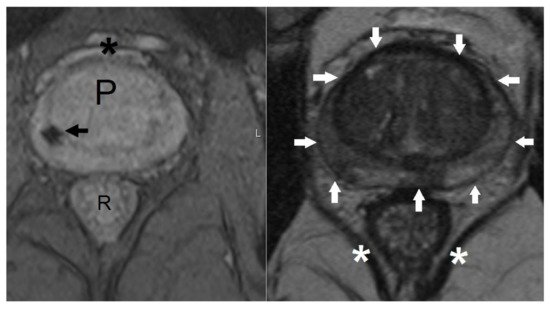

- Hentschel, B.; Oehler, W.; Strauss, D.; Ulrich, A.; Malich, A. Definition of the ctv prostate in ct and mri by using ct-mri image fusion in imrt planning for prostate cancer. Strahlenther. Onkol. 2011, 187, 183–190. [Google Scholar] [CrossRef] [PubMed]

- Debois, M.; Oyen, R.; Maes, F.; Verswijvel, G.; Gatti, G.; Bosmans, H.; Feron, M.; Bellon, E.; Kutcher, G.; Van Poppel, H.; et al. The contribution of magnetic resonance imaging to the three-dimensional treatment planning of localized prostate cancer. Int. J. Radiat. Oncol. Biol. Phys. 1999, 45, 857–865. [Google Scholar] [CrossRef]

- Steenbakkers, R.J.; Deurloo, K.E.; Nowak, P.J.; Lebesque, J.V.; van Herk, M.; Rasch, C.R. Reduction of dose delivered to the rectum and bulb of the penis using mri delineation for radiotherapy of the prostate. Int. J. Radiat. Oncol. Biol. Phys. 2003, 57, 1269–1279. [Google Scholar] [CrossRef]

- Sannazzari, G.L.; Ragona, R.; Ruo Redda, M.G.; Giglioli, F.R.; Isolato, G.; Guarneri, A. Ct-mri image fusion for delineation of volumes in three-dimensional conformal radiation therapy in the treatment of localized prostate cancer. Br. J. Radiol. 2002, 75, 603–607. [Google Scholar] [CrossRef] [PubMed]

- Parker, C.C.; Damyanovich, A.; Haycocks, T.; Haider, M.; Bayley, A.; Catton, C.N. Magnetic resonance imaging in the radiation treatment planning of localized prostate cancer using intra-prostatic fiducial markers for computed tomography co-registration. Radiother. Oncol. 2003, 66, 217–224. [Google Scholar] [CrossRef]